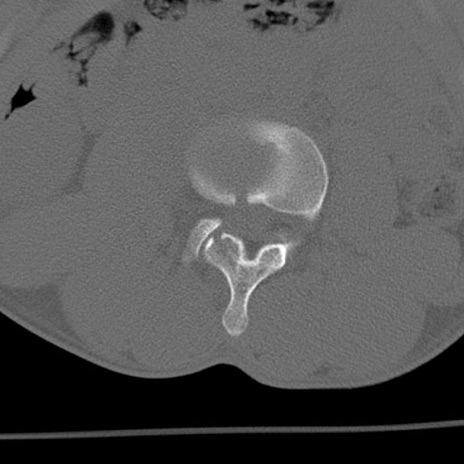

症例3 腰椎CT(横断像)

腰椎CT